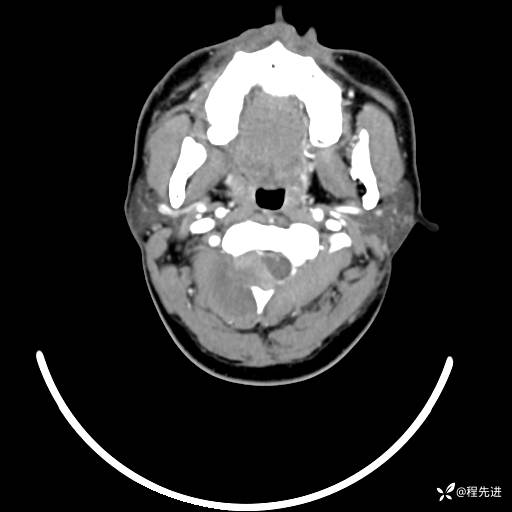

CT平扫+增强: